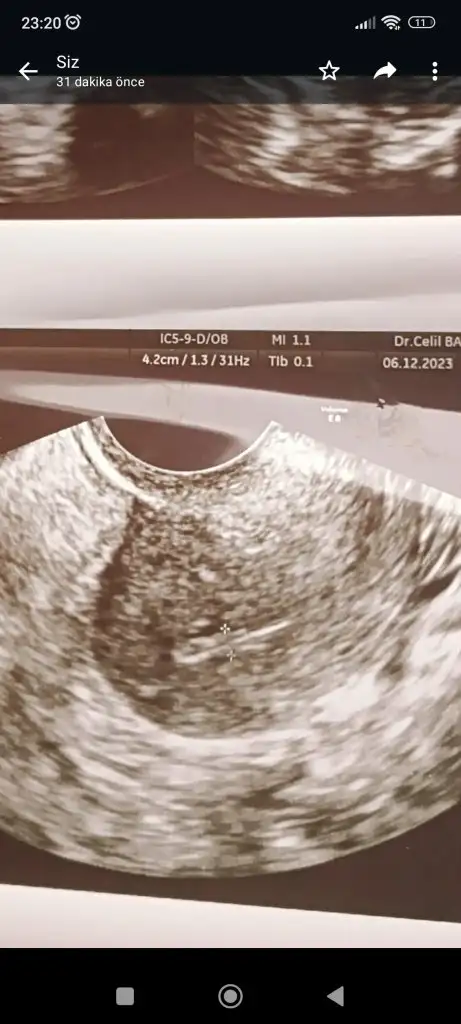

Çok ta anlaşılmıyor ya da düz bir açıdan çekilmiş bak benim eskilerden birini atıyorum şimdi ama resimden ziyada sağ alt köşesinde kaç ml olduğu yazıyor 1,87 2,44 cm yazıyor mesela senin kağıdın bir tarafında yok mu bu bilgi

• Screenshot_2023-12-06-23-28-49-432_com.miui.gallery.webp

27,7 KB · Görüntüleme: 80

Sizin en altta küçük bir tane yazıyor ama çok küçük diye mi acaba doktor yok dedi, o da olabilir. Evet progesteron testiyle anlaşılıyor o ay yumurtlama olup olmadığı, onu da ortalama döngü 28 gün üzerinden hesapla 21. gün istiyorlar, içinde kalcağına bence baktır canım aklında kuşku olmasın en azından

Ultrason fotoğrafımda işaretlenmiş iki nokta gördüm onların folikül olduğunu tahmin ediyorum ama dediğim gibi çok kötü bir doktora denk geldim kafam karıştı. Önerdiğiniz hormon testini vereceğim çok teşekkür ederim 💞🌺